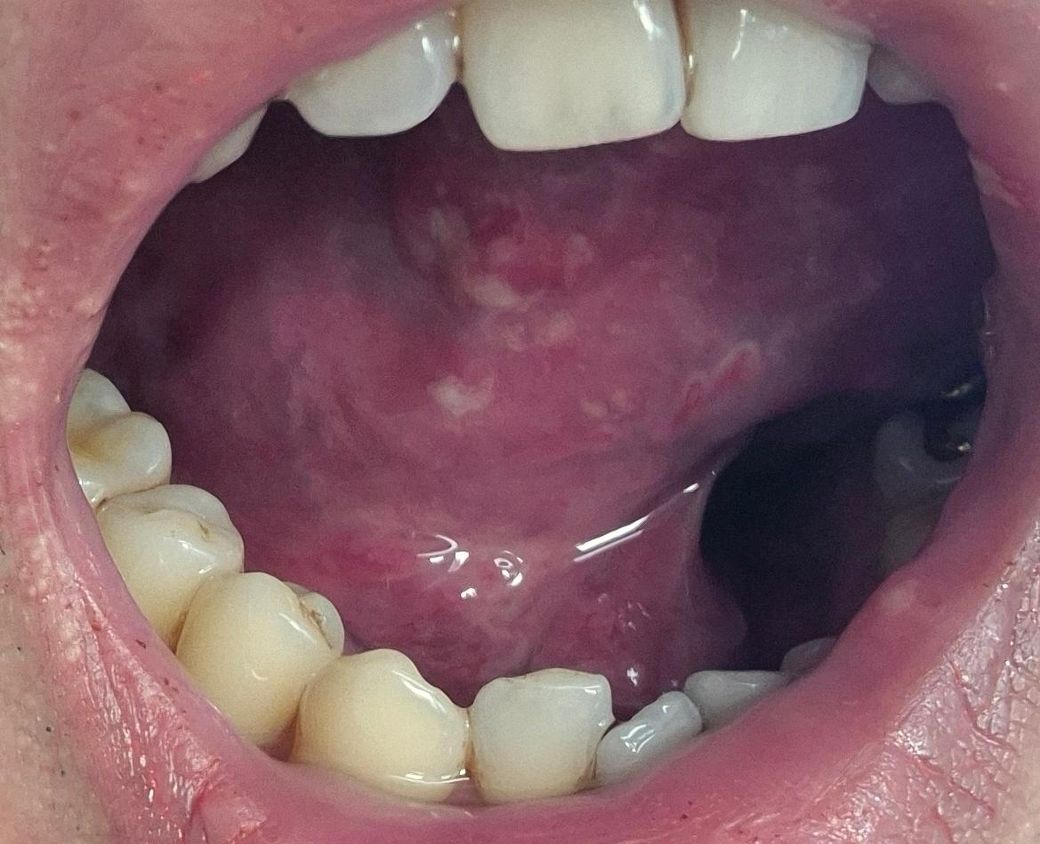

• 2번 째 사진